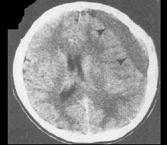

问题 患者,70岁,一周前头部碰到墙,后出现嗜睡2天入院,行头颅CT出现如图所示病变,应诊断为 ( )

选项 A、硬膜下出血 B、脑出血 C、蛛网膜下隙出血 D、脑梗死 E、硬膜外出血 一、单项选择题

答案 A